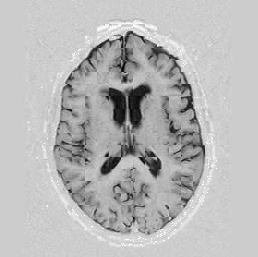

A long optimisation where I changed both the number of knot-points and the resolution is shown in Figures [*] and [*].

Figure: Multi-scale NRR withknot-points increase. From left to right, top then bottom: before NRR; after NRR, level 2, 4 knot-points; after NRR, level 1, 5 knot-points; after NRR, level 0, 10 knot-points. All stages comprised 10 iterations each.